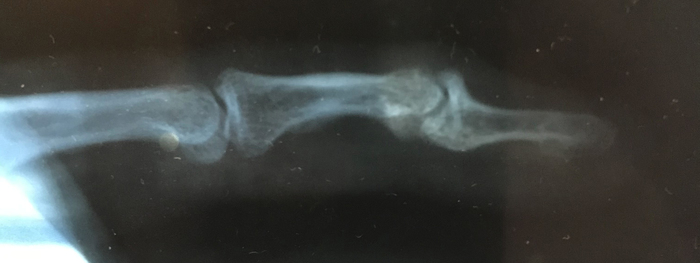

В 2019 году получил травму мизинца на левой руке в ходе выяснения отношений с одной пьяной тушей. Какая-то там травма пальца была не то, что на втором или третьем месте - я вообще это всерьёз не воспринимал. Быстро сходил в травматологию, сделали снимки, наложили повязку, что-то сказали и отпустили. Как только я переступил порог медицинского заведения, все мысли об этом меня покинули, и я опять погрузился в бытовуху. Да, это жёстко, когда человек забивает на себя и своё здоровье, жёстко, когда отношения летят в тартарары и ты вместе с ними, падая, периодически во что-то впечатываешься: "Опа, дно!". А потом "ой, нет, ещё не дно" - и так далее. И вот, я, Граф, мать его, Монте Кристо, вырываюсь из однокомнатного замка порочного круга, который я сам же себе когда-то создал, и мало-помалу начинаю приходить в себя, больше включаться в работу, налаживать отношения с внешним миром. Стал обращать внимание на своё здоровье: посещал стоматолога, гастроэнтеролога, лора, терапевта, ходил на лечебный массаж. Не обошёл стороной и травматолога, поскольку палец периодически не давал покоя - десятипальцевый набор текста, игра на гитаре, клавишах - всё это даёт нагрузку на связки, из-за чего под вечер палец начинает ныть и я закидываюсь обезболивающим.

Вердикт травматолога был такой: признаки неправильно сросшегося перелома основания дистальной фаланги со смещением. К дистальной фаланге подходят две связки - сгибатель и разгибатель. При травме откололся кусок кости, куда прикреплялся разгибатель, а потом это как-то неправильно срослось, палец внешне слегка выглядит деформированным. До конца не разгибается, при движении периодически пощёлкивает сустав. В 2020 году я получил квоту на операцию (только теперь сам не знаю, что за операцию и как они там собирались делать, я был уверен, что починят норм), сдал анализы и 2 апреля должен был явиться к ним. Ну а накануне, 1 апреля мне сообщили, что из-за ковида остановлены все плановые операции и шёл бы ты нахер, ну да, ну да. В общем, никто ничего толком не знал, я обзвонил всё, что только можно было обзвонить касательно моего вопроса и понял, что остался ни с чем. Спустя некоторое время я перебрался из своего Шира в славный город-на-Неве, Санкт-Петербург (вернее, в Ленобласть, и поначалу мне казалось, что я в Ашхабаде или Биробиджане, но сейчас привык). В Санкт-Петербурге есть отличный центр ортопедии и травмотологии ФГБУ "НМИЦ ТО им. Р.Р. Вредена". Ходят слухи, что там работают вредины лучшие хирурги-ортопеды. К одному из них я и пришёл на приём в надежде, что меня там похилят. Но, ознакомившись с моей проблемой, он выдал такое: "перелом сросся неправильно, протезы этого сустава нигде не изготавливают и выход тут только один - удалить сустав и скрепить фаланги под физиологическим углом ~30 град. Конечно, можешь не делать операцию и оттянуть срок насколько это возможно, но сустав деградирует и мало-помалу начнёт беспокоить всё больше, т.к. постепенно разрушается".

Снимки прилагаю.

Если загуглить в поиске по картинкам текст "mallet finger example xray" - выдаёт очень много случаев, схожих с моим, чтобы было более понятно.

P.S. на листе диагноза на фото написано примерно так: "Деформирующий артроз ДМФС на левой кисти. Возможно хирургическое лечение".